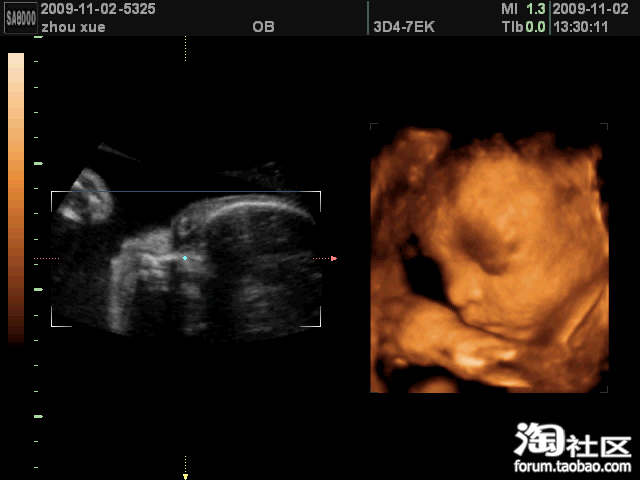

他先是用小手挡着嘴,不让我们看,高高的鼻子精巧的嘴型与我极像

我们特别想看看他的嘴,别有人什么裂的,他却像是有意的,总是一只手在嘴上挡着,照了一会惹急我了,一巴掌拍在肚皮上,清脆的一声响后,手终于拿开了,嘿嘿,当时把在场的人都看傻了,他们准是想我这当妈的够狠的,其实不是这样的。

这不吗,他动了以后,嘴就露出来了,长得很好哦